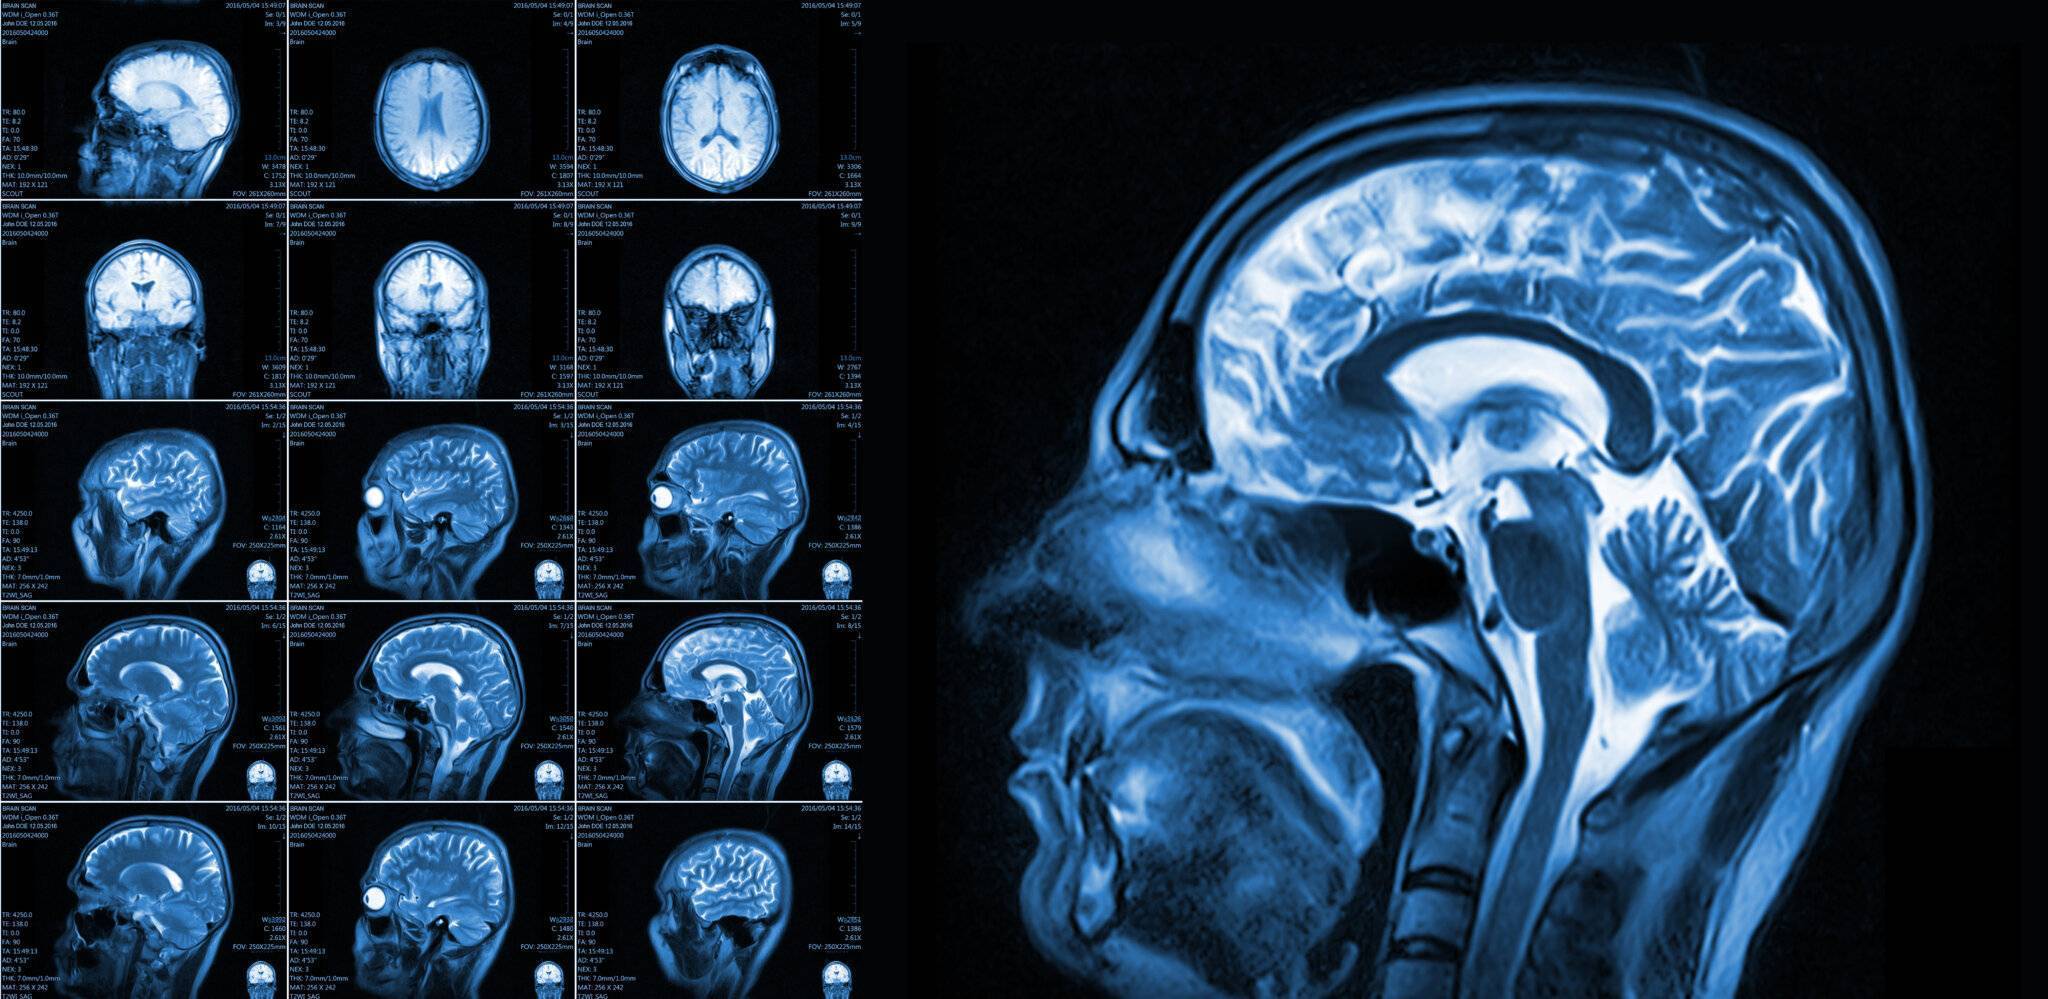

Eine Magnetresonanztomographie des Kopfes, kurz die MRT Kopf genannt, ist ein medizinisch bildgebendes Verfahren. Die MRT Kopf Untersuchung stellt mit Hilfe von Magnetfeldern und Radiowellen insbesondere unser Gehirn, Ohr, Nase und Nasennebenhöhlen, Augen, Kiefer, sowie genaue Strukturen detailliert dar. Vor allem bei diffusen oder langanhaltenden Kopfschmerzen kann eine MRT aufschlussreich sein. Vor allem ermöglicht eine Kopf MRT Einblicke in verschiedene neurologische Erkrankungen.

Eine Kopf MRT liefert Ärzte und Radiologen detaillierte Bilder. Zu sehen sind das Gehirn, Schädelknochen, Blutgefäße und anderer umgebende Gewebe im Kopfbereich.